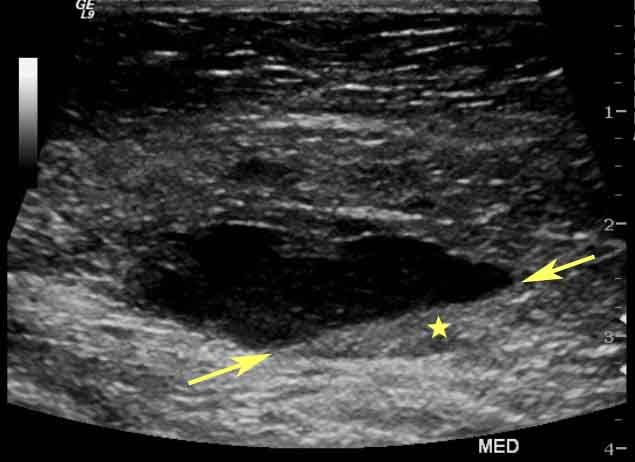

- BI-RADS 3: Hallazgo probablemente benigno, se recomienda seguimiento a corto plazo.

- BI-RADS 4: Lesión sospechosa que requiere biopsia para diagnóstico definitivo.

La inclusión del BI-RADS en el resultado del ultrasonido mamario permite establecer un plan de manejo personalizado. Por ejemplo, un BI-RADS 3 indica la necesidad de realizar ultrasonidos de control en intervalos específicos para observar posibles cambios.

En casos con BI-RADS 4 o 5, se recomienda realizar biopsias para confirmar o descartar la presencia de cáncer y así diseñar un tratamiento adecuado.